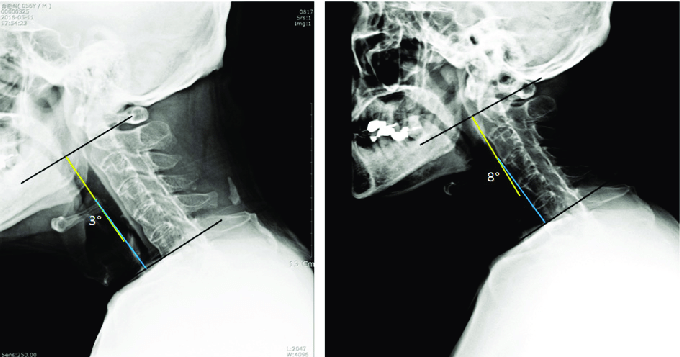

Baseline Neck Screening Motion X-ray

What is involved in a Baseline Screening Motion X-Ray?

What is involved in a BaselineScreening Motion X-Ray?

Scenario 2 – If you have had injury in the past, and perhaps either feel fine right now or are still experiencing regular pain, a second unexpected injury could happen. A baseline screening, where we perform a Motion X-ray study of your neck will show the current functional health of your neck, even if it is not perfect. Because a future injury can cause you to start having pain or worsen your current pain, being able to compare any scan changes from the new injury to the baseline scan is crucial.

In all cases, the biggest benefit is the ability to compare how your neck functions during a repeat Motion X-ray after having an additional injury.

In order to make a screening Motion X-ray most valuable, a repeat screening every two to three years is recommended so that the functional status of your neck is as current as possible.